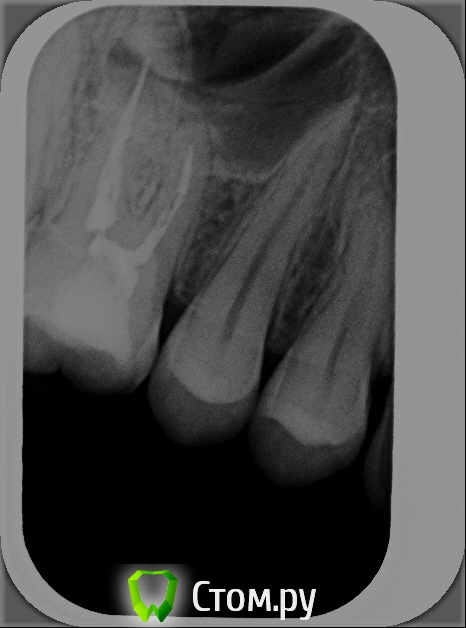

xSlon Опубликовано 13 августа, 2014 Поделиться Опубликовано 13 августа, 2014 Доброго времени суток!Прошу вашей помощи по сложному зубу, который не могут вылечить уже очень длительное время. Около 3х лет назад обнаружил, что при постукивании по 16му зубу(он был запломбирован совсем давно, не помню даже где и в каком году) появляется небольшая боль. Зуб не мешал, не доставлял беспокойств, но решив, что в таких случаях нужно действовать превентивно, пошел к стоматологу и рассказал о проблеме. Он посмотрел зуб(без вскрытия), сказал что никаких признаков боли не видит и считает что нужно удалять нерв. Поскольку зуб проблем не доставлял, я отказался.В течение этих трех лет состояние не ухудшалось, но я еще два раза ходил к разным стоматологам, описывал симптомы, они смотрели зуб, никаких признаков болезни не видели и советовали заниматься зубом когда он будет доставлять настоящие неудобства.В середине октября 2013 года ситуация ухудшилась, зуб начал периодически не сильно болеть, реагировать на холодное и горячее. В середине декабря ситуация сильно ухудшилась, зуб начал сильно болеть, сильно реагировать на холодное и горячее, сильно болеть даже при простом касании. Я обратился в стоматологию1 к врачу1, где мне вскрыли зуб, сказали что обнаружили под пломбой кариес, из-за кариеса произошло воспаление нервов и нужно удалять нервы в зубе. Боль была очень значительной, я не раздумывая согласился. Мне вскрыли зуб, поставили обезболивающее(или лекарство - точно не знаю), и сказали прийти через 7 дней, боль прошла. Через 7 дней мне обработали каналы и запломбировали Metapex'ом, сказали прийти в феврале(возможно еще удалили лекарство, точно не помню). В феврале мне за 1 посещение запломбировали постоянно каналы и за 2е посещение запломбировали зуб. К середине февраля лечение закончилось, жалоб не было. Единственное - удивляло что зуб, несмотря на удаление нервов, по старому реагирует на постукивание небольшой болью, но я не придал этому большого значения.Спустя 2 месяца, в середине апреля, остро заболел тот же самый зуб, с теми же симптомами - сильная боль, сильная реакция на холодное и горячее, сильная боль при касании. Врач1 был в отпуске, поэтому я пошел к Врачу2 в ту же самую Стоматологию1. Описал ситуацию, Врач2 посмотрела мою карточку, вскрыла зуб, осмотрела его, сказала что где-то должен быть 4й канал, но она не может его найти, сказала что вставила куда-то в зуб лекарство, сказала прийти через неделю.Боль утихла, пришел через неделю к тому же Врачу2, повторно вскрыли зуб, повторно поставили лекарство, но Врач2 сказала что 4го канала, который там должен быть, она не видит. Посоветовала обратиться к другому врачу, возможно, в другую стоматологию Через неделю, уже в начале мая, пришел повторно, запломбировали каналы Metapex'ом, поставили временную пломбу. По совету знакомых, в начале июня обратился к частному Врачу3, который специализируется на работе под микроскопом. Описал ей ситуацию, она вскрыла зуб, нашла четвертый канал, вставила туда лекарство, сказала прийти через неделю. Через неделю реакция зуба на слабые постукивания сохранилась, на приеме у Врача3 поставили более сильное лекарство(насколько я помню, с антибиотиком), прописала дополнительно в течении 5 дней пропить сильные антибиотики, сказала прийти через 10 дней. Через 10 дней, в конце июня, та же реакция зуба сохранилась. На приеме у Врача3 решили окончить лечение, потому как Врач3 на следующий день уходила в отпуск, а я, через несколько дней, уезжал в командировку. Перед отъездом пошел в Стоматологию1 к Врачу2, чтобы снять лекарство и временно запломбировать каналы и поставить временную пломбу. Врач2 сказала, что при вскрытии зуба она увидела 4й канал, попыталась определить длину канала с помощью прибора, используя самый тонкий инструмент(как я понял - это некая игла, подсоединенная к прибору, ее всовывают в канал, чем ближе кончик иглы к концу канала, тем сильнее он пищит), определить длину канала ей не удалось. Она предположила, что либо канал очень узкий, либо он изгибается, поэтому не удается дойти до конца канала.В командировке, в середине июля обновлял временную пломбу(от нее отвалился небольшой кусочек) в Стоматологии2, вкратце описал проблему Врачу4, он посоветовал использовать(дословно с листочка, который он мне дал) пломбировку материалом для к/к Forfenan Forident(резорцин-формалиновая паста). Сказал, что при таком методе, воспаленный нерв полностью обволакивается пастой, которая гермитизирует нерв, не давая разиваться воспалительному процессу. Сам воспаленный нерв остается, но организм, со временем, справляется с ним сам.Вернувшись из командировки, я пошел, по советам родственников, в Стоматологию3, к Врачу5. Описал ситуацию, сделал панорамный и прицельный снимки. Врач5, не вскрывая зуб, сказала что считает, что необходимо применить метод депофореза. Прошу вас, пожалуйста, посоветовать, каким образом вылечить этот зуб? Стоит ли попробовать резорцин-формалиновую пасту? Стоит ли делать метод депофореза? Возможно есть какие-то другие методы лечения? Прикладываю все снимки зуба из Стоматологии1Панорамный снимок из Стоматологии3, сделан 12 августа. https://yadi.sk/i/_hIqGP1IZaT4Y Ссылка на комментарий

xSlon Опубликовано 14 августа, 2014 Автор Поделиться Опубликовано 14 августа, 2014 Добавлен прицельный снимок 16го зуба от 12го августа. К сожалению, не нашел, как отредактировать первый пост. Ссылка на комментарий

Scrabble Опубликовано 31 августа, 2014 Поделиться Опубликовано 31 августа, 2014 Я вижу, что Вам запломбировали каналы термафилами-причём два носителя введены в дистальный, а не в мезиальный щёчный корень. В качестве силера(пасты) использовался форфенан? Если это так, то нужно всё распломбировать, полностью удалить форфенан-и ждать, пока стихнет симптоматика. Ссылка на комментарий